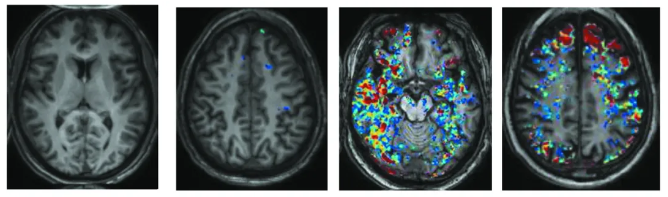

血脑屏障的老化:大脑扫描结果显示,随着年龄的增长,血脑屏障中的漏洞会越来越多。30岁时血脑屏障没有出现漏洞(1)。42岁时,蓝色斑点的出现表示血脑屏障出现了少量的漏洞(2)。65岁时,红色和黄色斑点代表了更多漏洞的出现(3)。76岁时,血脑屏障的漏洞仍在继续增加(4)。

在过去的5年里,我们已经获得了足够的证据证明这一过程也发生在人类身上。我们利用示踪分子标记了20多至70多岁的人群的血脑屏障漏洞信号。通过磁共振成像,我们可以看到,随着人们年龄的增长,血脑屏障上的漏洞会逐渐增加。